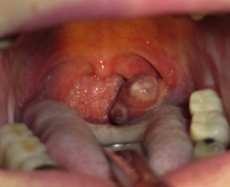

中咽頭癌